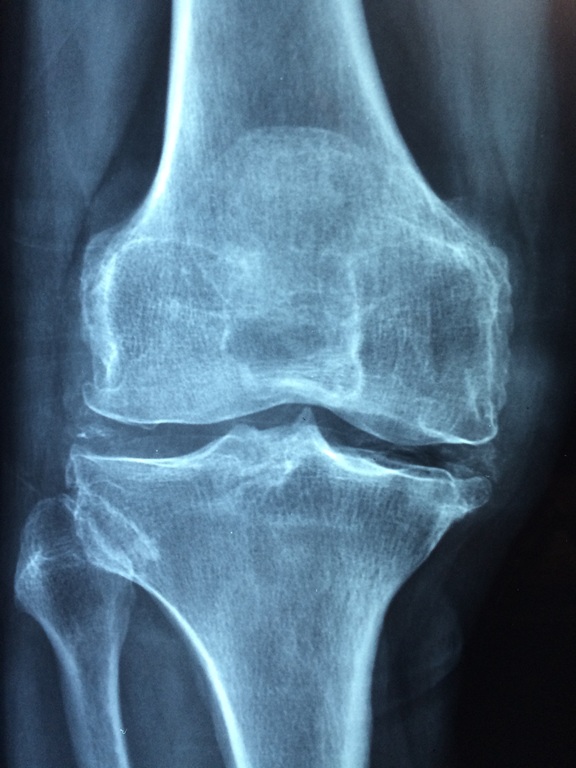

골다공증으로 고생하시는 분들이 의외로 많다. 증상이 보여도 인정하지 않는 분들도 있다. 골밀도가 떨어져 골을 지탱하고 있는 구조물이 함께 무너지는 증상이다. 생각해보자. 건물을 지탱하고 있는 기둥에 손상이 가면 그 건물은 오래갈 수 없다. 항상 무너질까 불안하다. 마찬가지다. 골다공증이 노화 등의 원인으로 자연의 순리처럼 받아들이지 말고 골다공증에 좋은 음식을 섭취하고 운동으로 건강한 삶을 살면 그 얼마나 좋을까 하는 생각이 든다. 나이가 들어 어디 가고 싶어도 갈 수 없는 상황이 오면 안 된다. 내 발로 걸어서, 움직이면 그보다 더 좋은 환경이 어디 있을까 싶다.

인체에는 수명이 다해 제 기능을 못하는 오래된 뼈를 용해시켜 없애주는 파골세포와 새로운 뼈를 생성하는 조골세포가 있다. 두 세포가 뼈의 균형을 맞추기에 건강하게 움질 일 수가 있는 것이다. 골다공증의 원인 중 제일 비중을 많이 차지하는 것이 노화와 폐경이다. 이때 파골세포의 작용을 억제하는 호르몬인 에스트로겐의 분비가 감소하게 되어 파골세포의 기능만 활발히 일 어나 게 된다. 이것이 대표적인 골다공증의 원인이다. 보통 혈액검사를 통해 CRP라는 급성기 반응물질의 양이 변화하는 양상을 보면서 염증 수치를 확인할 수 있다. 정상수치는 0.5mg~1.0mg/dL인데, 수치가 높을수록 염증을 의심해볼 수 있다.